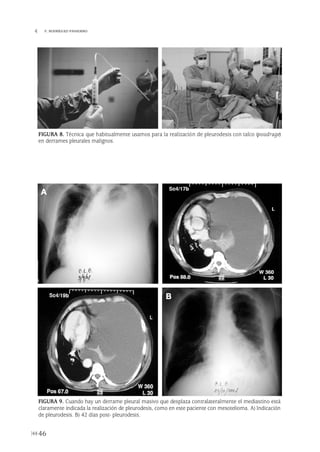

negativos, la toracoscopia es el procedimien-

to de elección en los pacientes con sospecha

de derrame pleural maligno.

En los casos en los que se sospecha el diag-